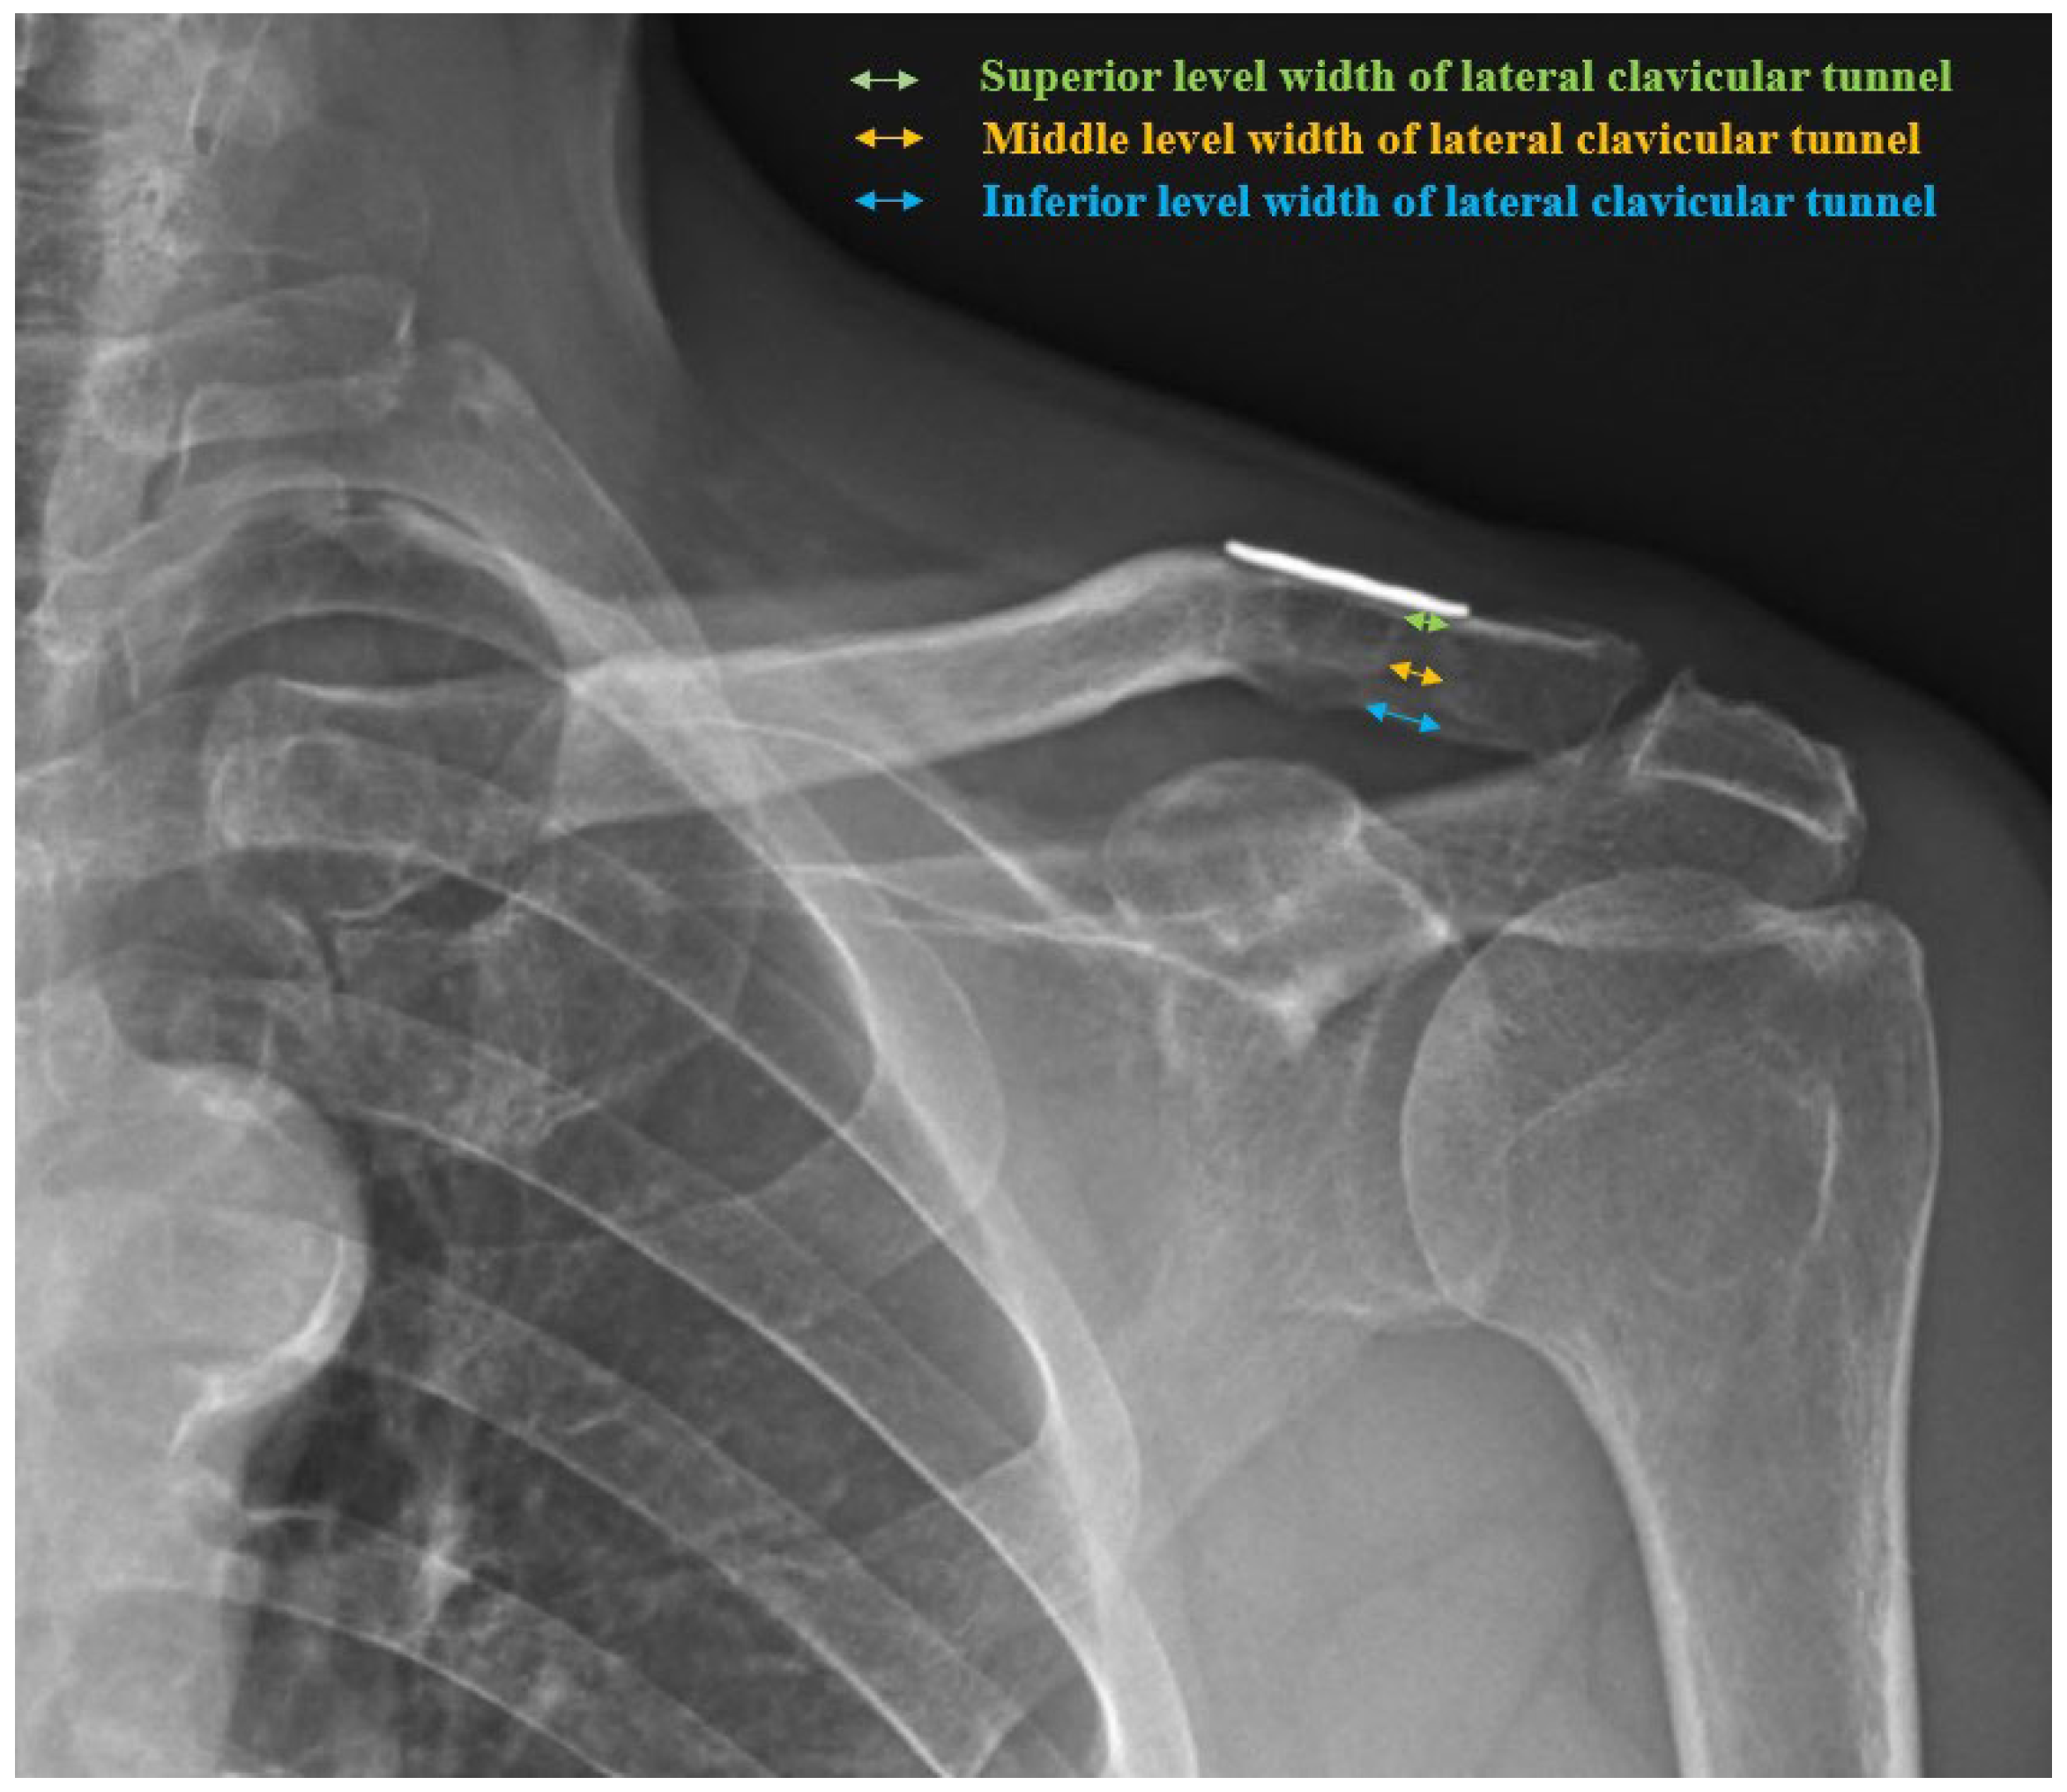

Anteroposterior (AP) images of the affected shoulder and both clavicles were taken immediately postoperatively and at 3-month, 6-month, 12-month, and 24-month follow-ups, and the widths of the medial and lateral clavicular tunnels were measured at the superior, middle, and inferior levels in millimeters (Figure 2), and these values were compared to assess the degrees of widening.

Figure 2.

A 24-month follow-up AP radiograph of an affected shoulder showing widening of the medial and lateral clavicular tunnels after combined CC stabilization and AC capsule repair. The widths of the lateral clavicular tunnel were measured at the superior (green arrow), middle (orange arrow), and inferior (blue arrow) levels in millimeters (mm).